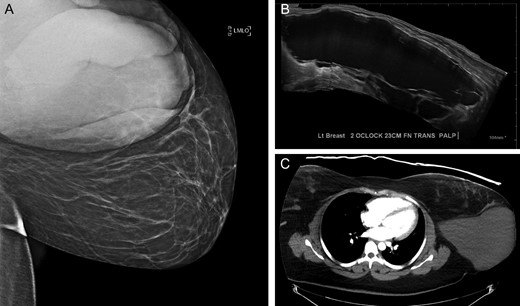

In this most recent visit, her physical examination was normal apart from the left breast mass, and the patient showed no obvious signs of distress. Breast exam was consistent with her previous diagnosis, showing a roughly 20 × 10 cm2 lobulated, fluid-filled, left breast mass. Given the large size, imaging was recommended to the patient in order to better evaluate the extent of the mass. Diagnostic mammogram revealed a 23.6 × 15.7 × 15.1 cm3 lobulated mass in the lateral left breast, again categorized as BI-RADS 2A (Fig. 1A). This was confirmed via ultrasound and computed tomography (CT) (Fig. 1B and C). Given her history and the results of cytopathology, we concluded that this was most likely a persistent cystic lymphangioma of the breast, but repeated pathologic analysis to exclude the possibility of malignant transformation or breast cancer.

Results of pre-operative (A) mammography (B) ultrasound and (C) computed tomography (CT).